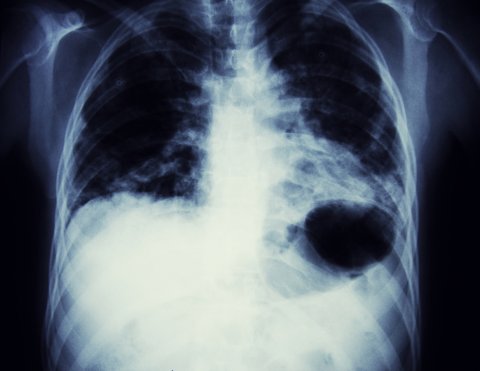

Lungenkrebs Imagebild

Österreich ist bisher die Frage der Einführung eines Lungenkarzinom-Screenings noch nicht so wirklich angegangen.